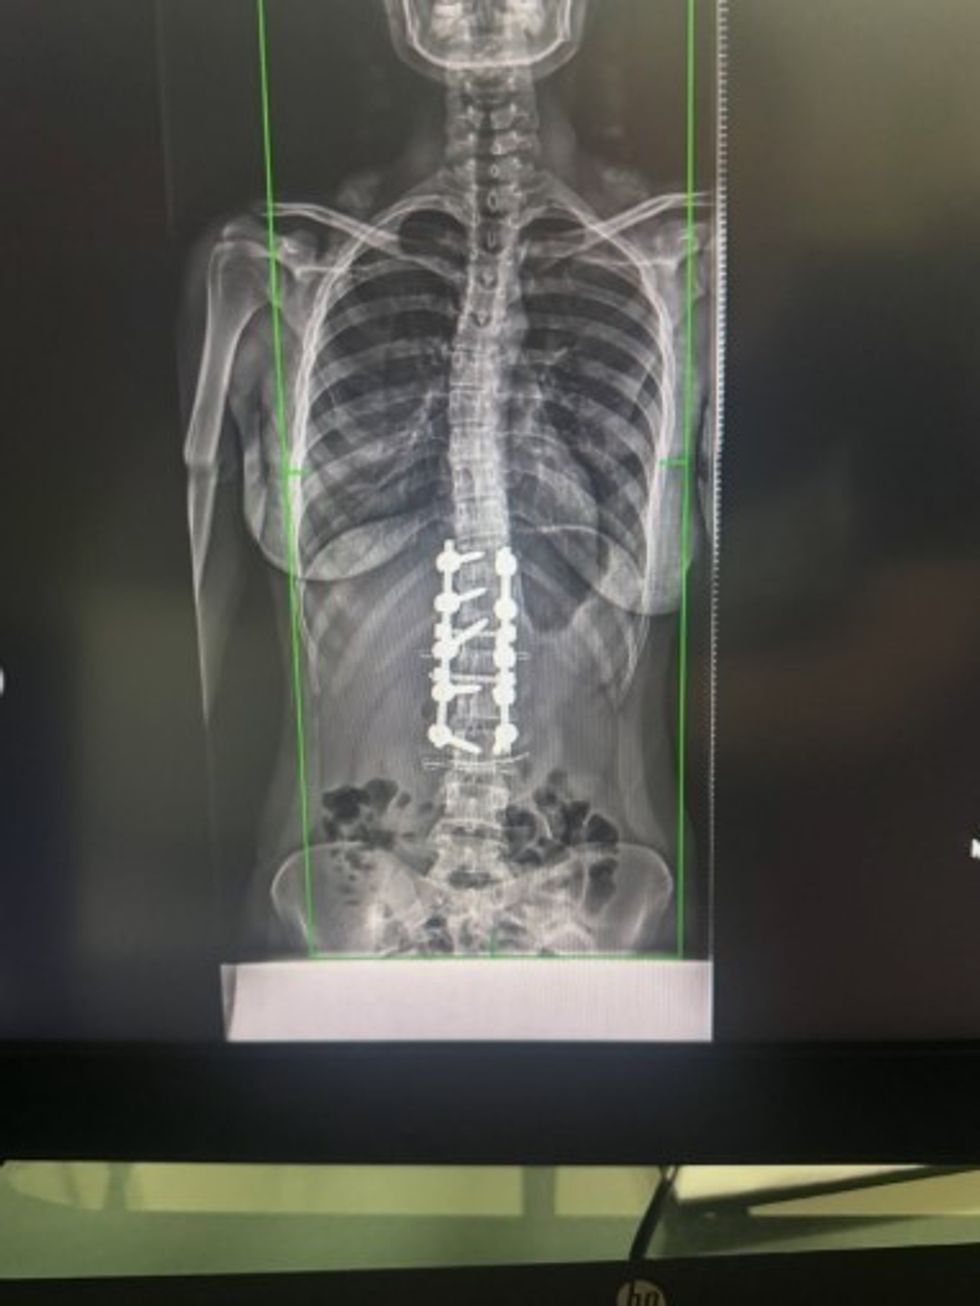

Ish-banorja e Big Brother VIP Kosova, Anisa Veseli, ka ndarë me ndjekësit e saj në Instagram një përvojë shumë të rëndësishme dhe emocionuese: operacionin që ajo ka bërë për skoliozën.

Ajo ka postuar një fotografi nga shtrati i spitalit, ku tregon se ka kaluar me sukses këtë ndërhyrje kirurgjikale të vështirë.